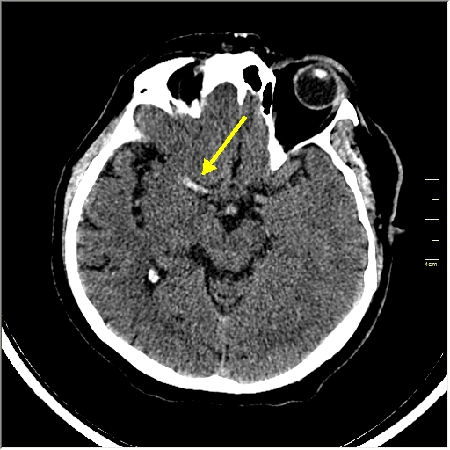

Ответ: Обратите внимание на правую среднемозговую артерию (MCA); М1 сегмент гиперденсен; сравните с другой стороной.

Этот признак называется [Dense MCA sign]; за счёт наличия тромбоза в её просвете. Этот признак является одним из ранних указующих КТ признаков при ишемическом инфаркте головного мозга. Более подробно об этом вы можете прочитать здесь: http://www.radiologyassistant.nl/en/483910a4b6f14.